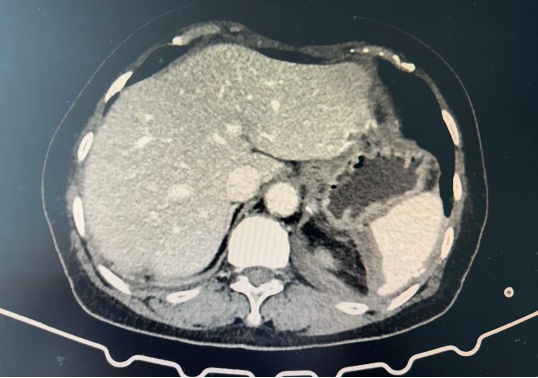

术后影像